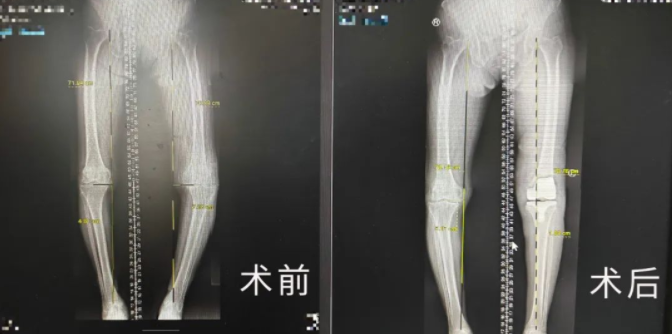

对于这种疾病来说,KL分级:IV级已属晚期,需要进行膝关节置换手术治疗。在与家属沟通后,为了使萧奶奶术后创伤更小、康复更快、关节功能更佳、假体生存率更长,手术团队决定在Mako关节置换机器人辅助下,为老人进行左膝关节置换术。

从业40多年、拥有3万余台手术经验的关节外科张传开主任介绍,在Mako机器人的辅助下进行手术,可以将手术精度控制在亚毫米级!相较传统手术只能凭借医生自主意识判断的方式来讲,这大幅提升了手术精准度、降低手术风险及并发症的发生率、延长假体使用寿命,这对高龄老年患者的术后康复来说也大有益处。

与传统骨科手术相比,Mako机器人能够辅助手术医生准确快速地完成定位及假体植入,其精准度远超传统术式,解决了手术医生“看不准”、“拿不稳”的问题,同时在术后也使患者创伤更小、康复更快、关节功能更佳、假体生存率更长,生活质量大大提高。